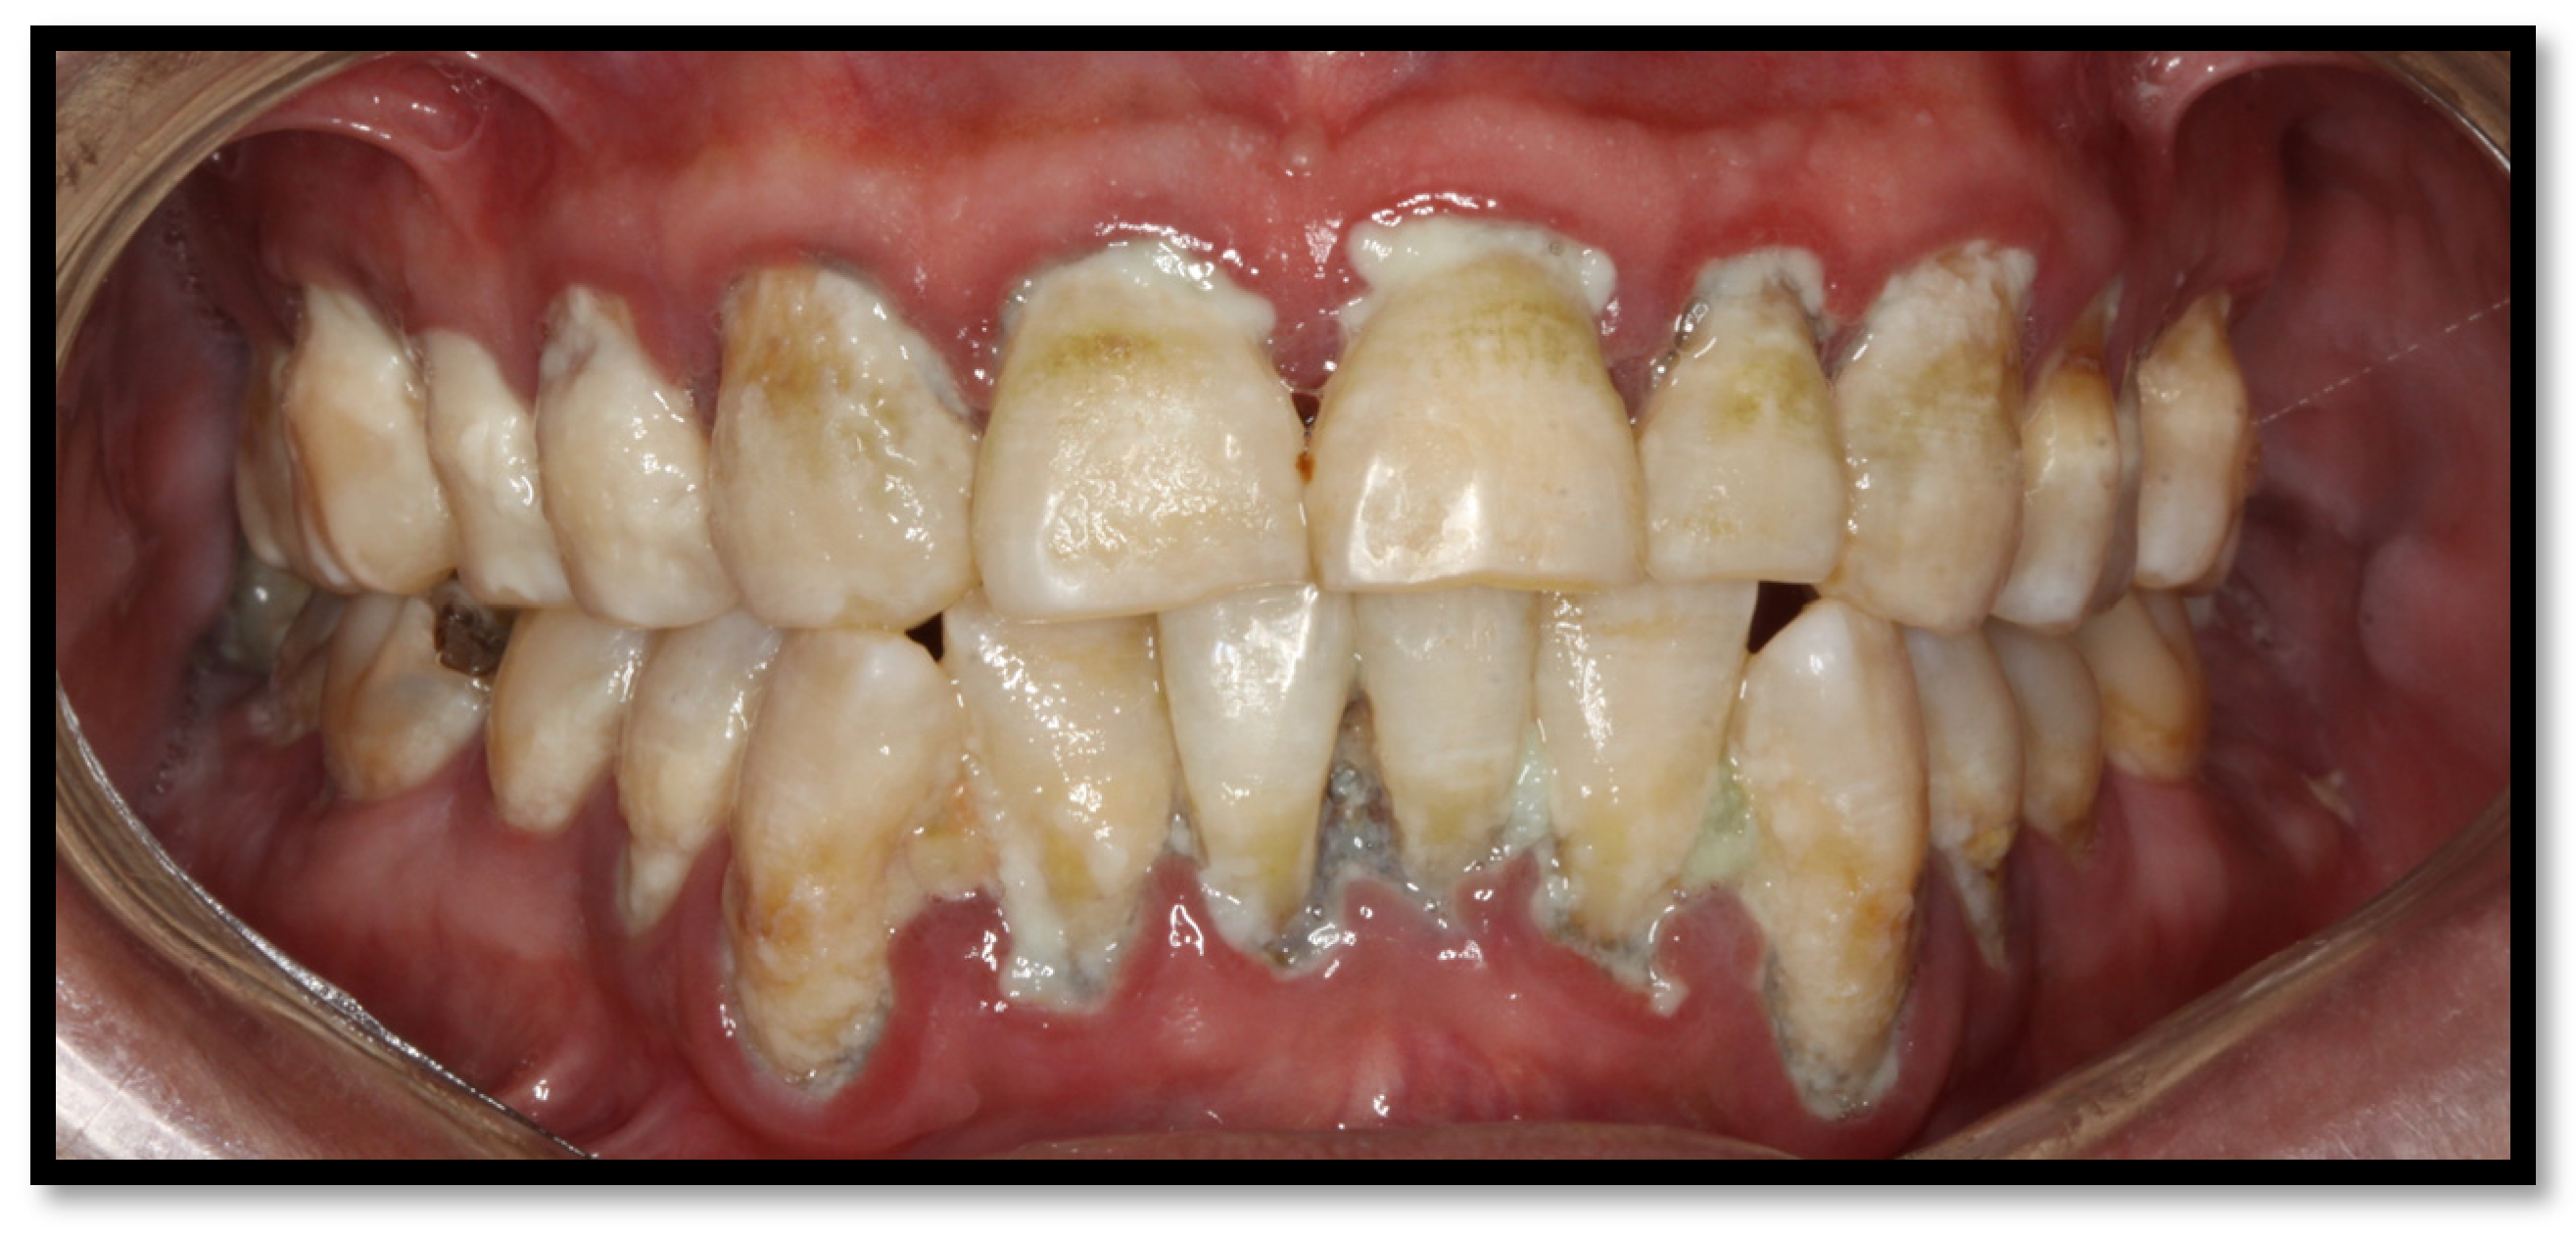

3. Periodontal Disease

3.1. Linear Gingival Erythema

3.2. Periodontitis

3.3. Necrotizing Gingivitis (NG)

3.4. Necrotizing Periodontitis (NP)